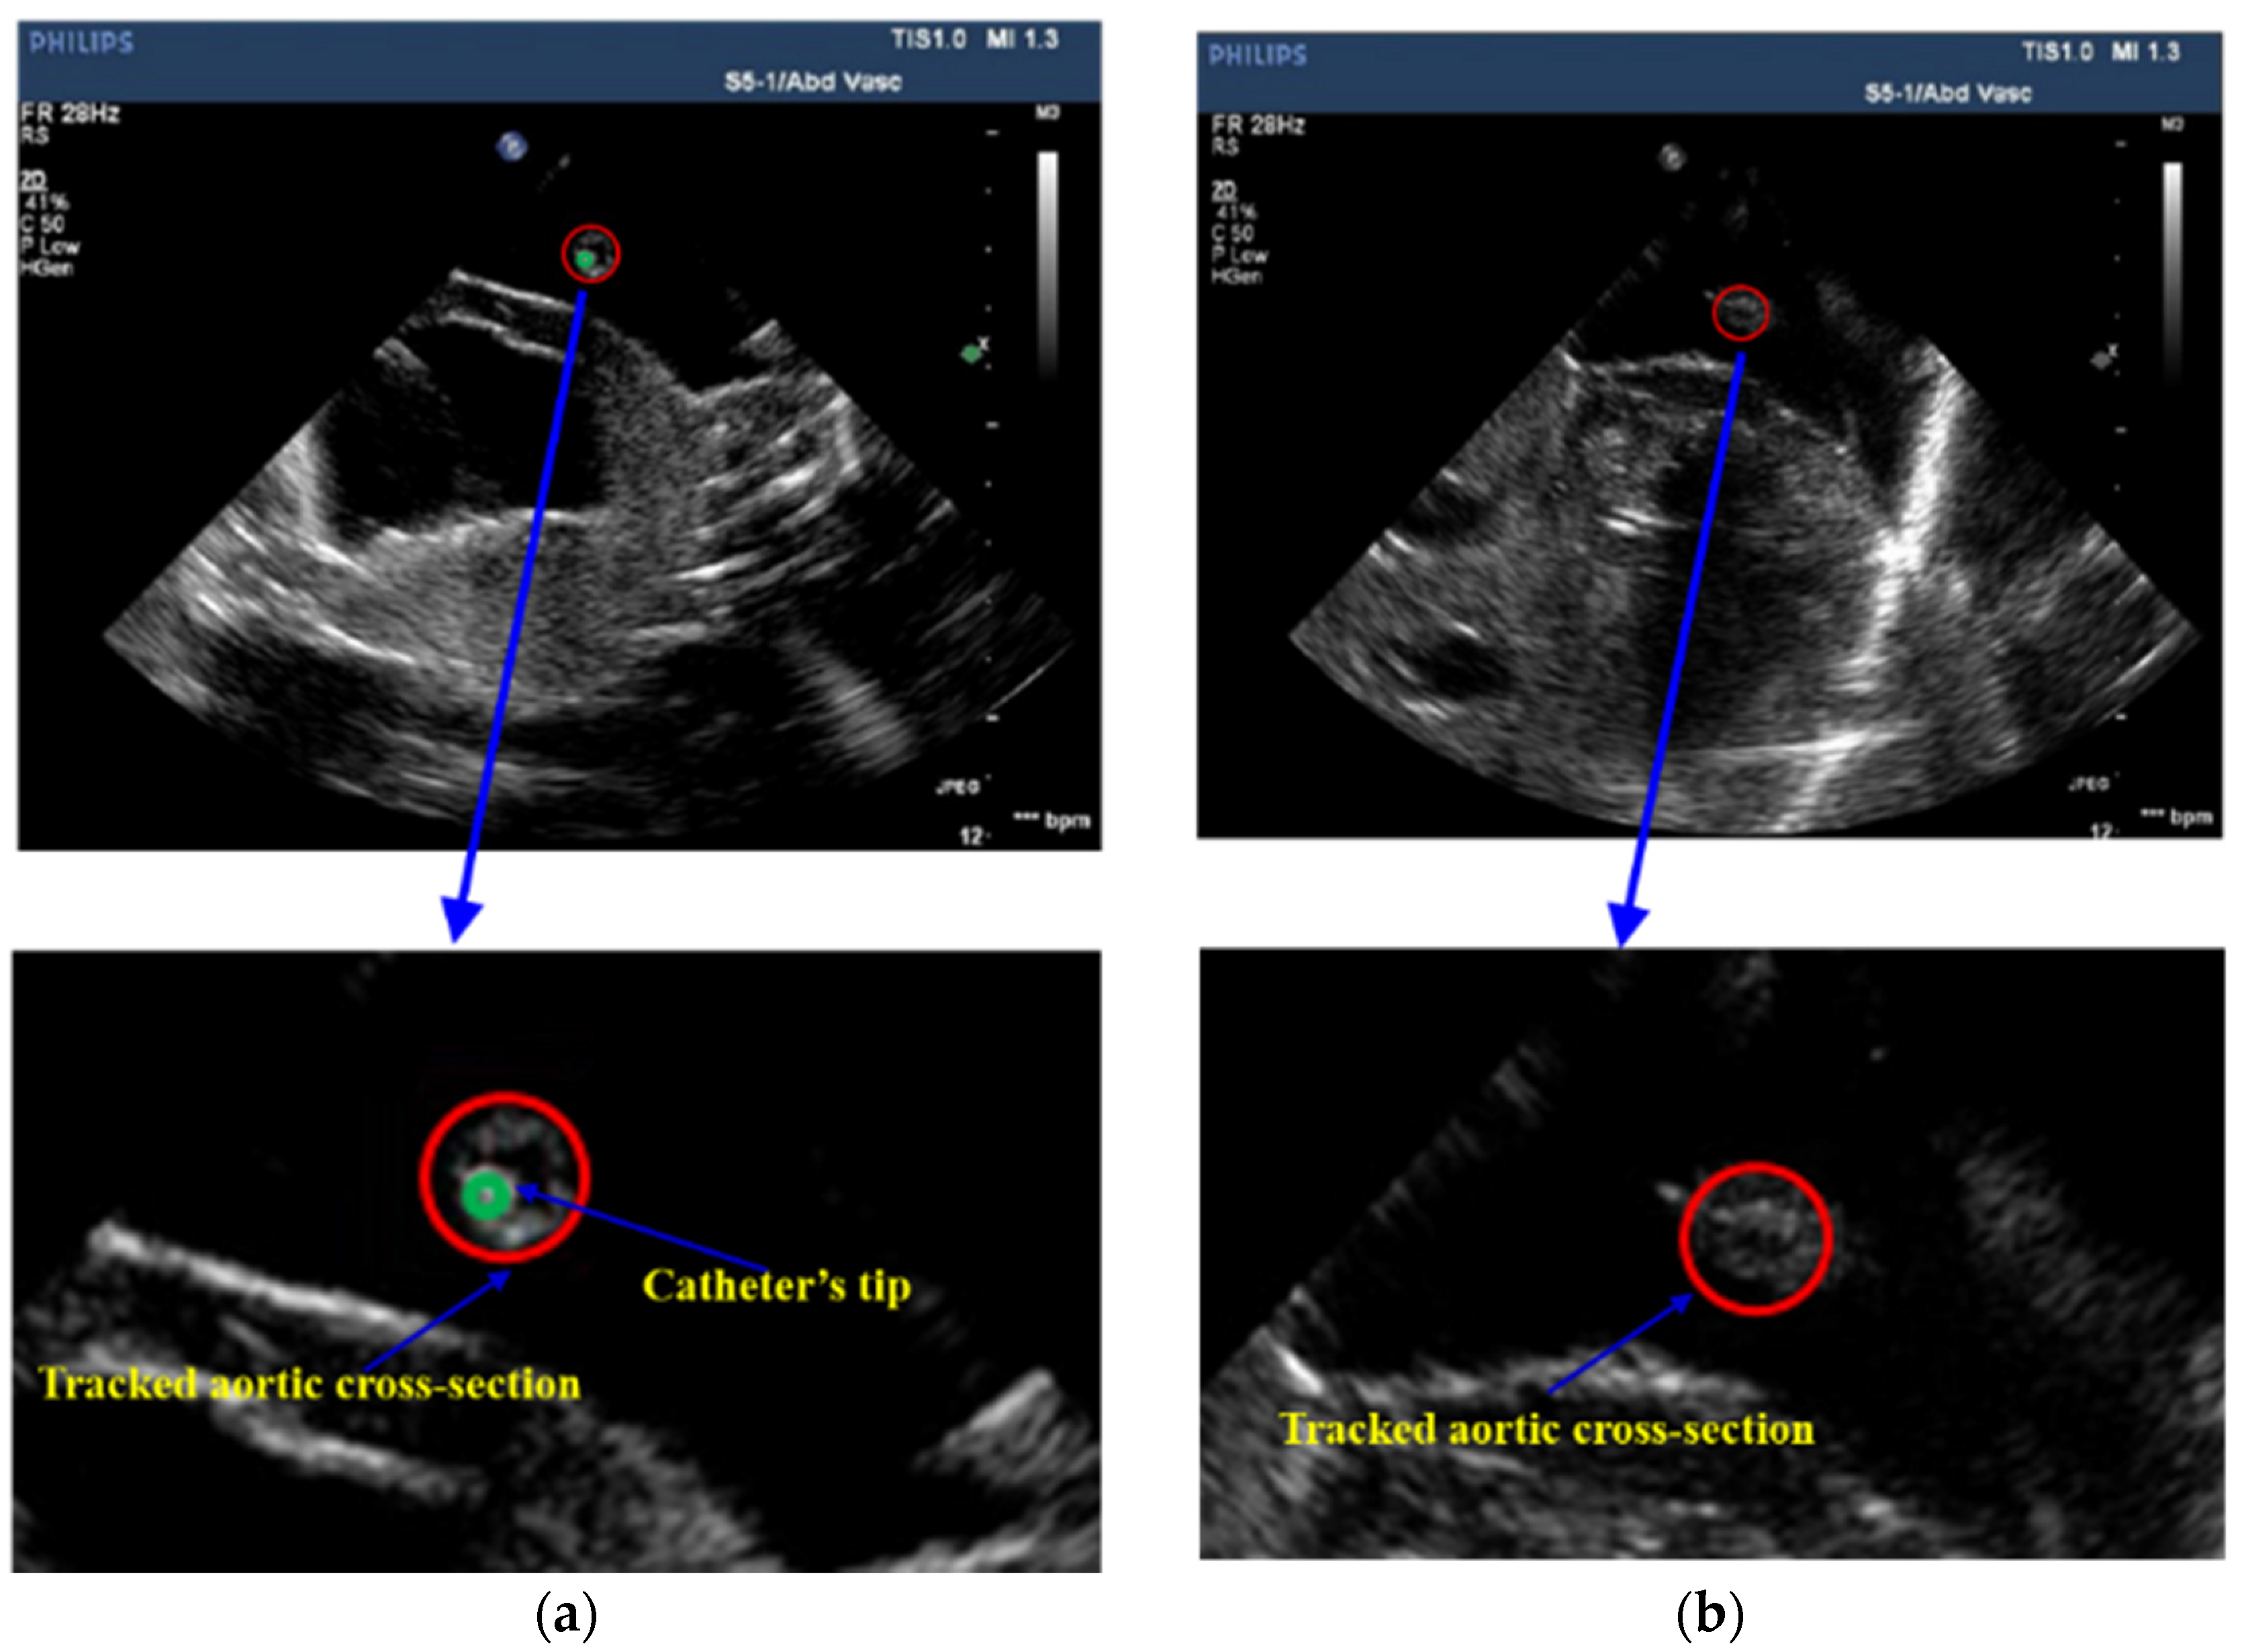

After tracking aortic cross-sections in US images, threshold technology is applied to obtain those pixels whose intensities are higher than 220 inside the aortic cross-section. The centroid of those pixels is the detected position of the cross-section of the catheter. In Figure 7, the red circle represents the tracked aortic cross-section and the green point is the located tip of catheter. Based on the positions of the catheter’s tip, the 3D trajectory of the catheter is acquired. Figure 8 shows two trajectories of the catheter, including an automatic trajectory of the catheter from our multi-feature particle filter tracking method and a 3D trajectory from the manually delineative catheter’s tip. The distance between the manual trajectory and automatic trajectory using multi-feature particle filter tracking method is 1.48 mm.

The image guidance interface and information during the intervention are illustrated in Figure 10. Under the guidance of a global navigation map (Figure 10a–c), the relative position between interventional catheter and 3D cardiac structure is displayed intuitively to navigate the catheter to the target. However, there is the limitation that the morphological information of aortic model, especially the lesion’s position, is blurred (Figure 10c). On one hand, to evaluate the vessel reconstruction error of global information, we measured the average outer radius of manually reconstructed aortic model from global MR image, and compared the average outer radius with the actual outer radius of aortic phantom (4.5000 mm). We selected 40 transverses of the reconstructed aortic model to acquire an average outer radius. The resolution of MR images is 0.4871 mm and the acquired reconstruction error of global navigation is 1.1241 mm. On the other hand, the catheter was navigated to the target using global information, and the distance between the catheter arrival position and the target was measured by using coronal and sagittal X-ray projections images from C-arm (Fluoroscan Insight, HOLOGIC, Boston, MA, USA). This distance is treated as targeting error of global navigation (See Figure 11a) and the acquired targeting error is 2.8701 mm.

Comparatively, in the case of a global map plus local navigation information, the user can be guided to insert catheter along the preoperative planning path. Meanwhile, the local navigation information (Figure 10d–f), further provides the user with critical details of the target point. Firstly, to evaluate the vessel reconstruction error of local navigation information, we calculated the average outer radius of the automatically reconstructed aortic model from segmented IVUS images, and compared this average outer radius with the actual radius of aortic phantom. The resolution of IVUS images is 0.0175 mm and the acquired reconstruction error of local information is 0.2217 mm. Secondly, to evaluate the targeting error of catheter intervention, we captured coronal and sagittal X-ray projections when the catheter was navigated to the target by using global plus local information. These projections images are measured (See Figure 11b) and the acquired targeting error is 1.7214 mm. This experiment shows that the new US navigation system which integrates global and local information can improve upon the navigation system that relies on a global navigation map alone.

Figure 7. Tracking result of aortic cross-section and catheter’s tip in US images, (a) the US image which contains the catheter’s tip; (b) the US image which does not contain the catheter’s tip.

Figure 11. (a) Two perpendicular X-ray projections were taken to verify the targeting distance between the catheter arrival position and target point during catheter intervention under the global guidance alone; (b) Two perpendicular X-ray projections under the global map plus local navigation.